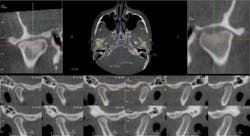

Here are multiple cross sections of both the left and right condyles revealing both active and nonactive condylar degenerative joint disease.